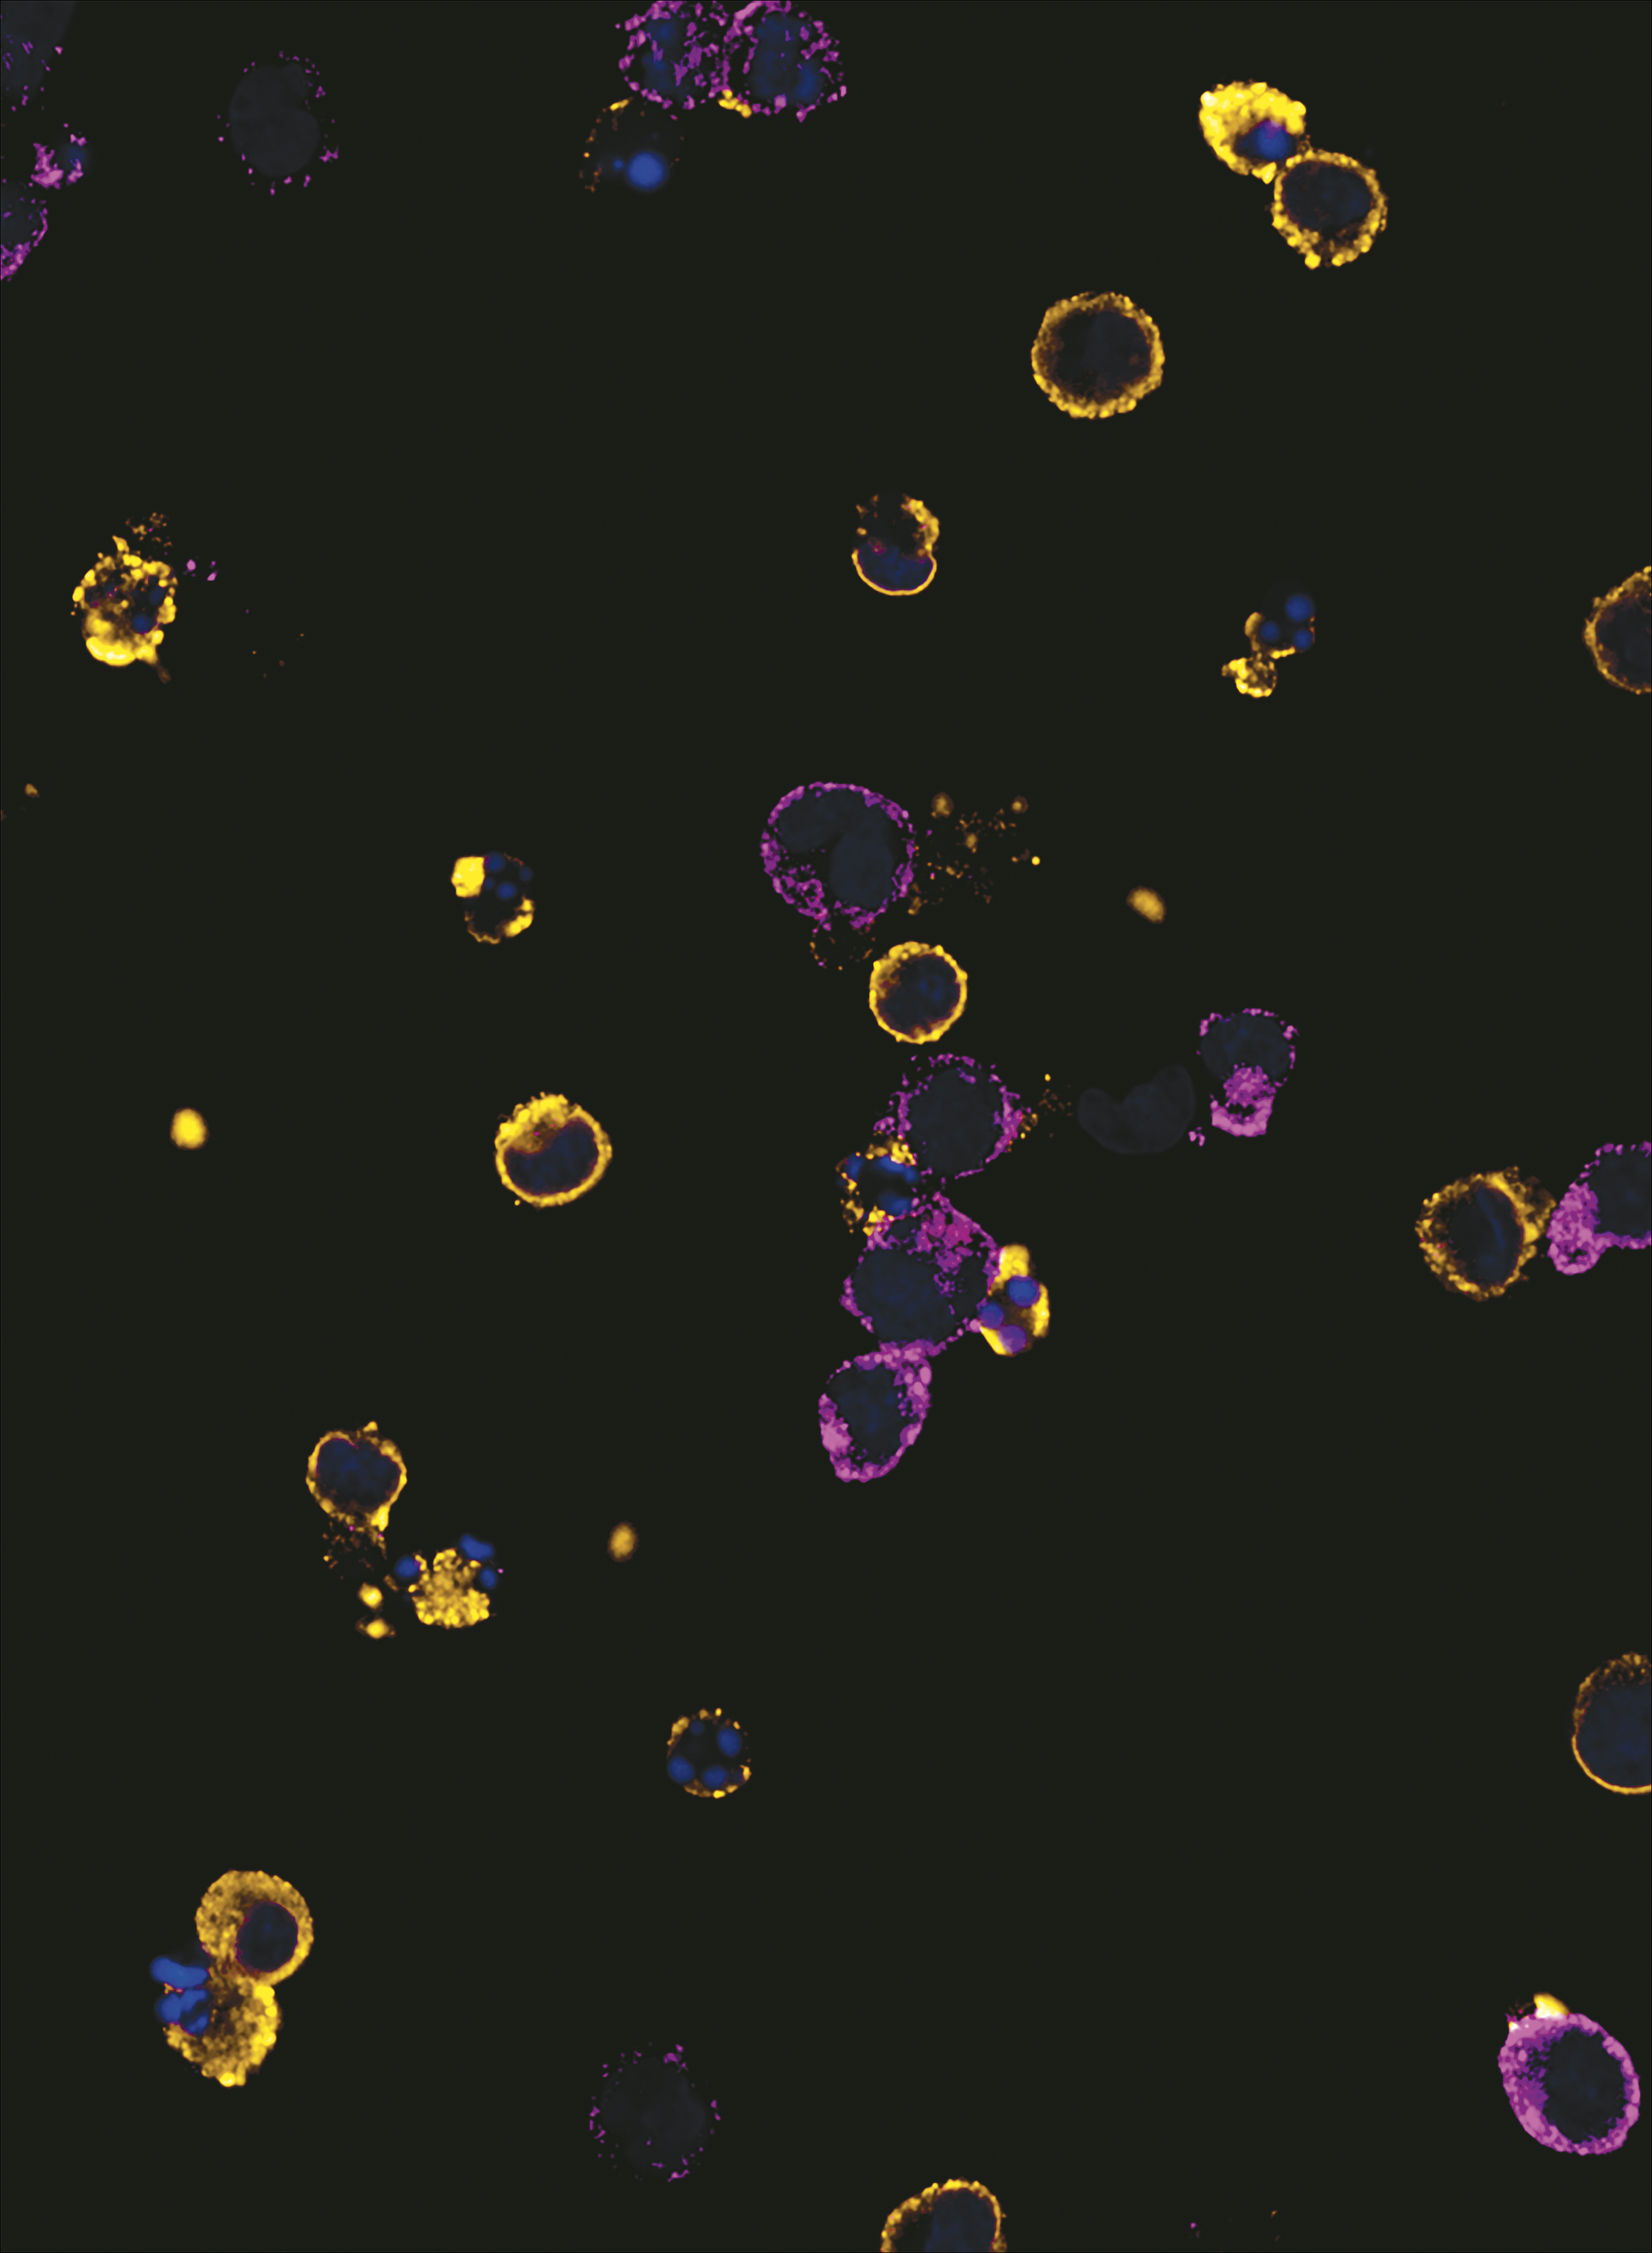

Induction of interferon-induced transmembrane protein 3 (IFITM3) in human megakaryocytes prevents dengue virus infection. Mature CD34+-derived megakaryocytes expressing IFITM3 (magenta) are protected against dengue virus infection (yellow). Nuclei were stained with TO-PRO-3 (blue). See the article by Campbell et al on page 2013.